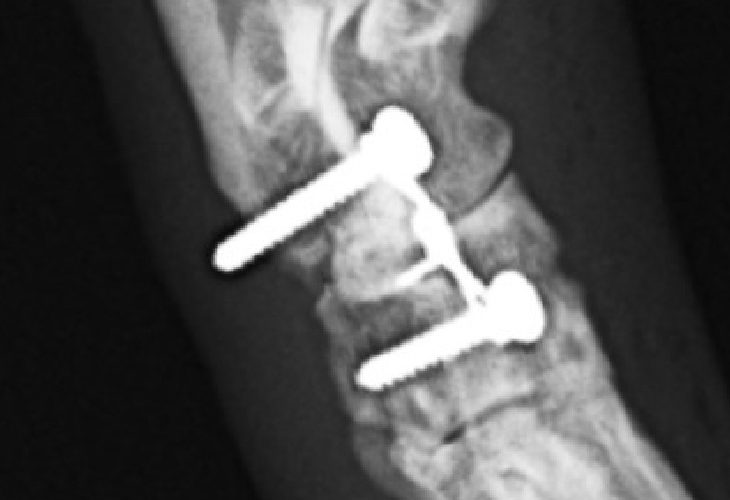

足根関節脱臼